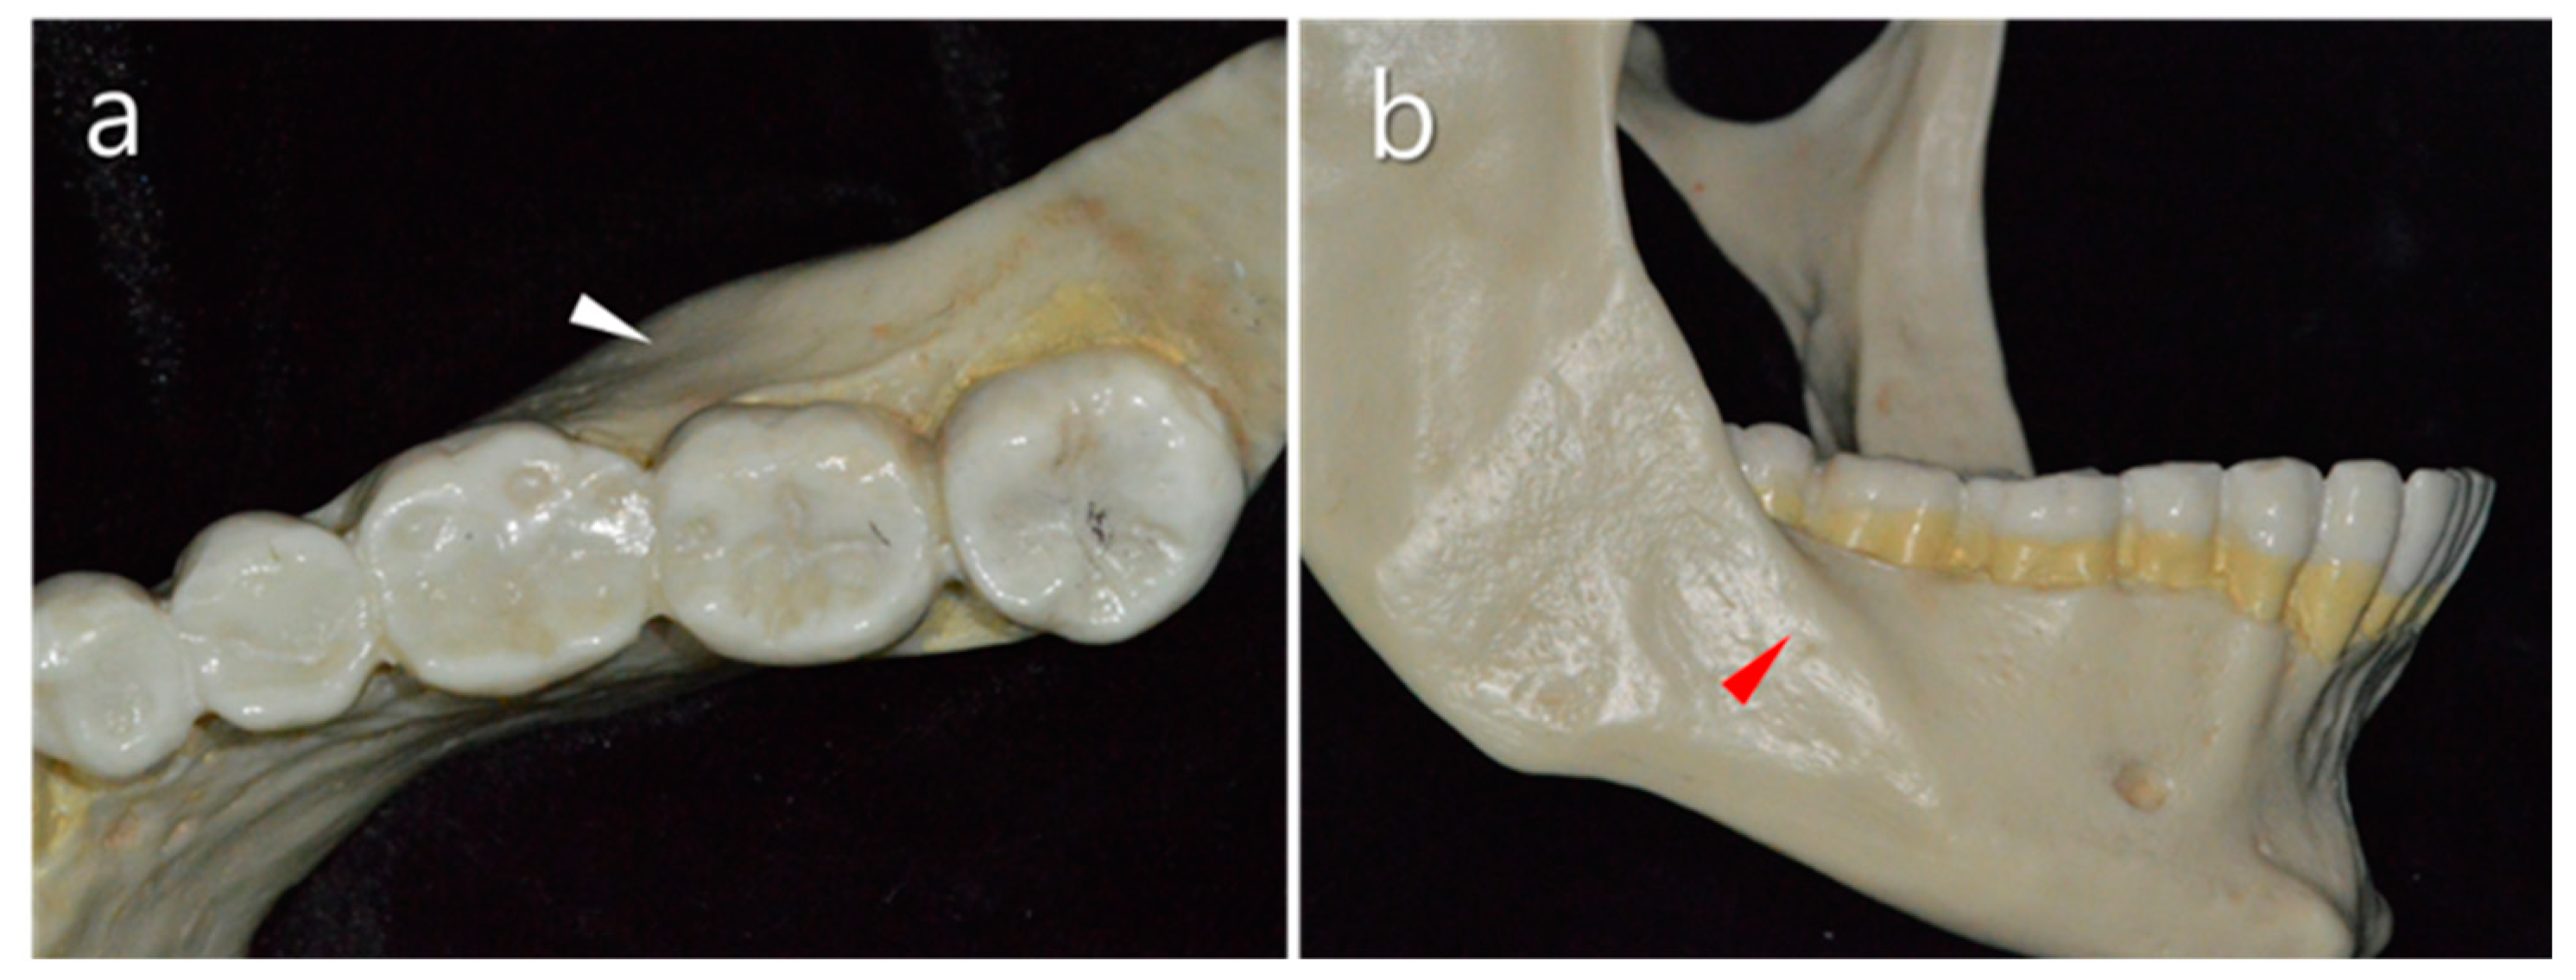

2.1. Thickness of the Buccal Bone

2.2. Vestibular Fornix

2.5. Distolingual Root